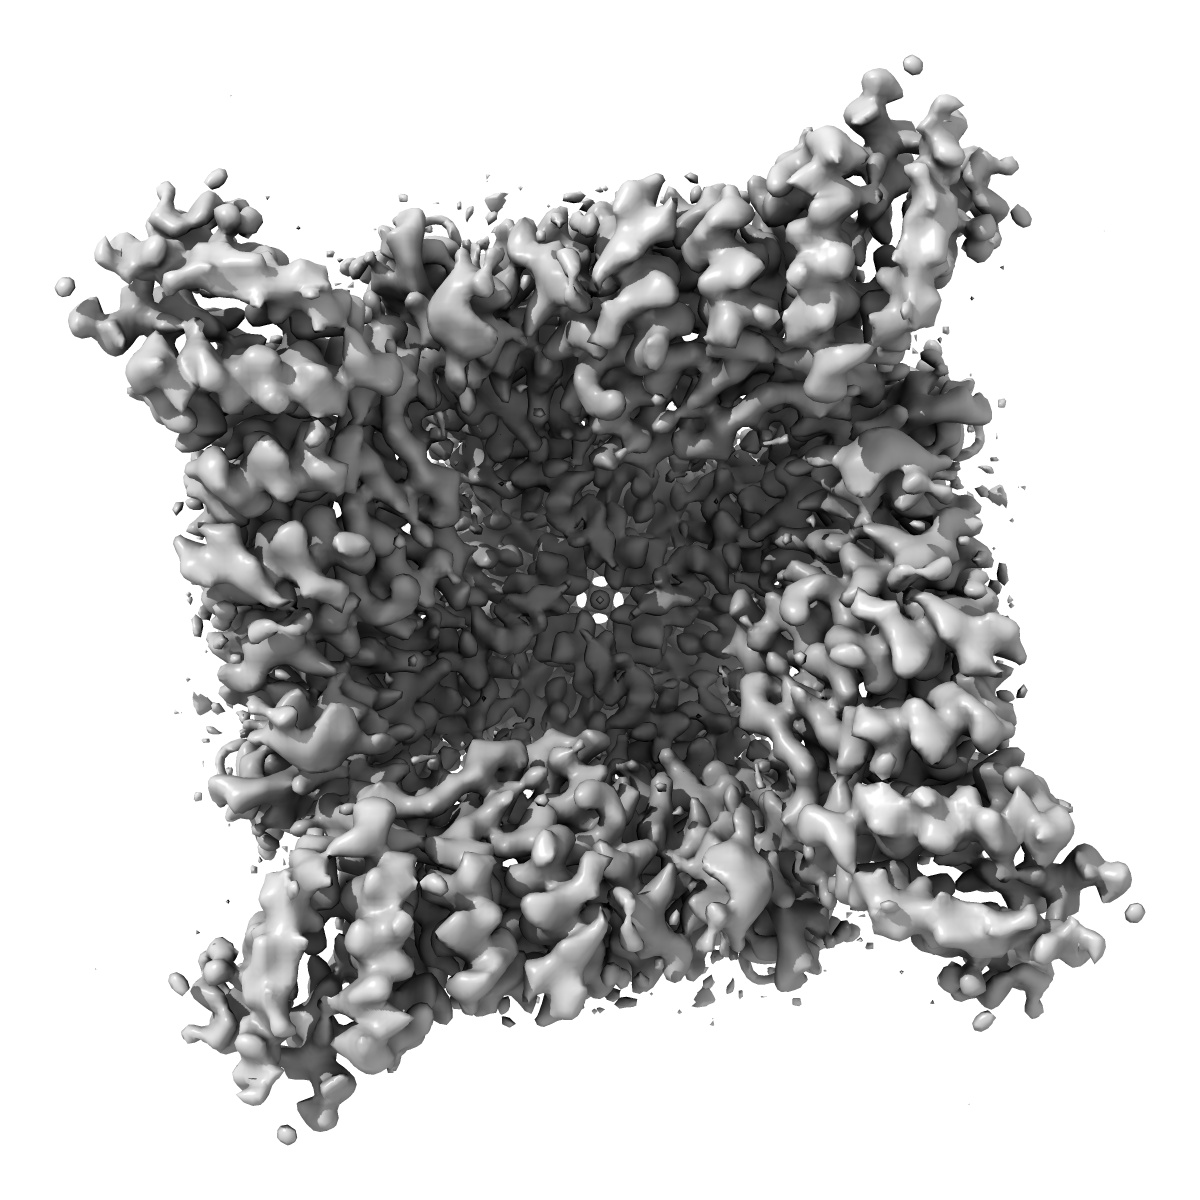

Inactivated-state cryo-EM structure of human TRPV3 in presence of tetrahydrocannabivarin (THCV) in cNW30 nanodiscs

Single-particle3.63 Å

Sample: full-length human TRPV3 in complex with THCV

Fitted models: 8v6m